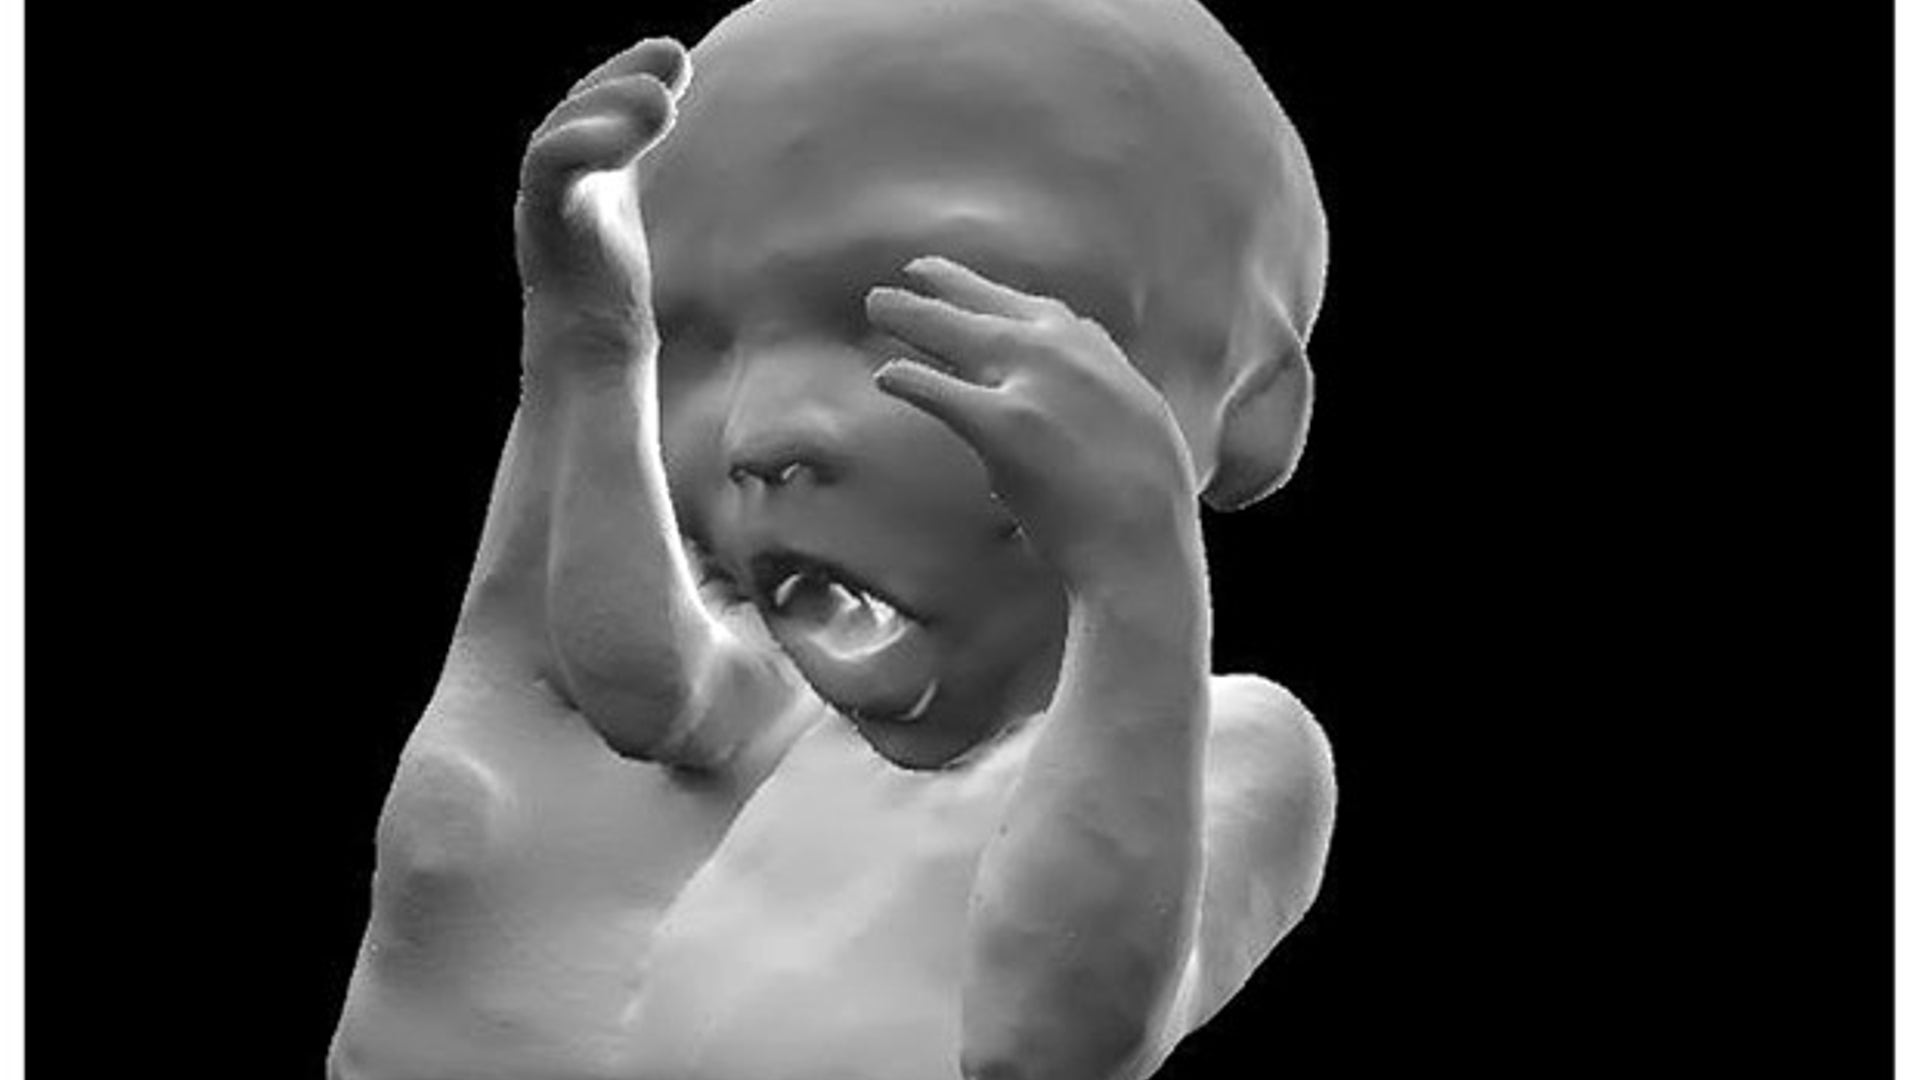

A new revolutionary scanning technique allows expectant mothers to hold three-dimensional models of their unborn children.

New Fetus Scanning Technique